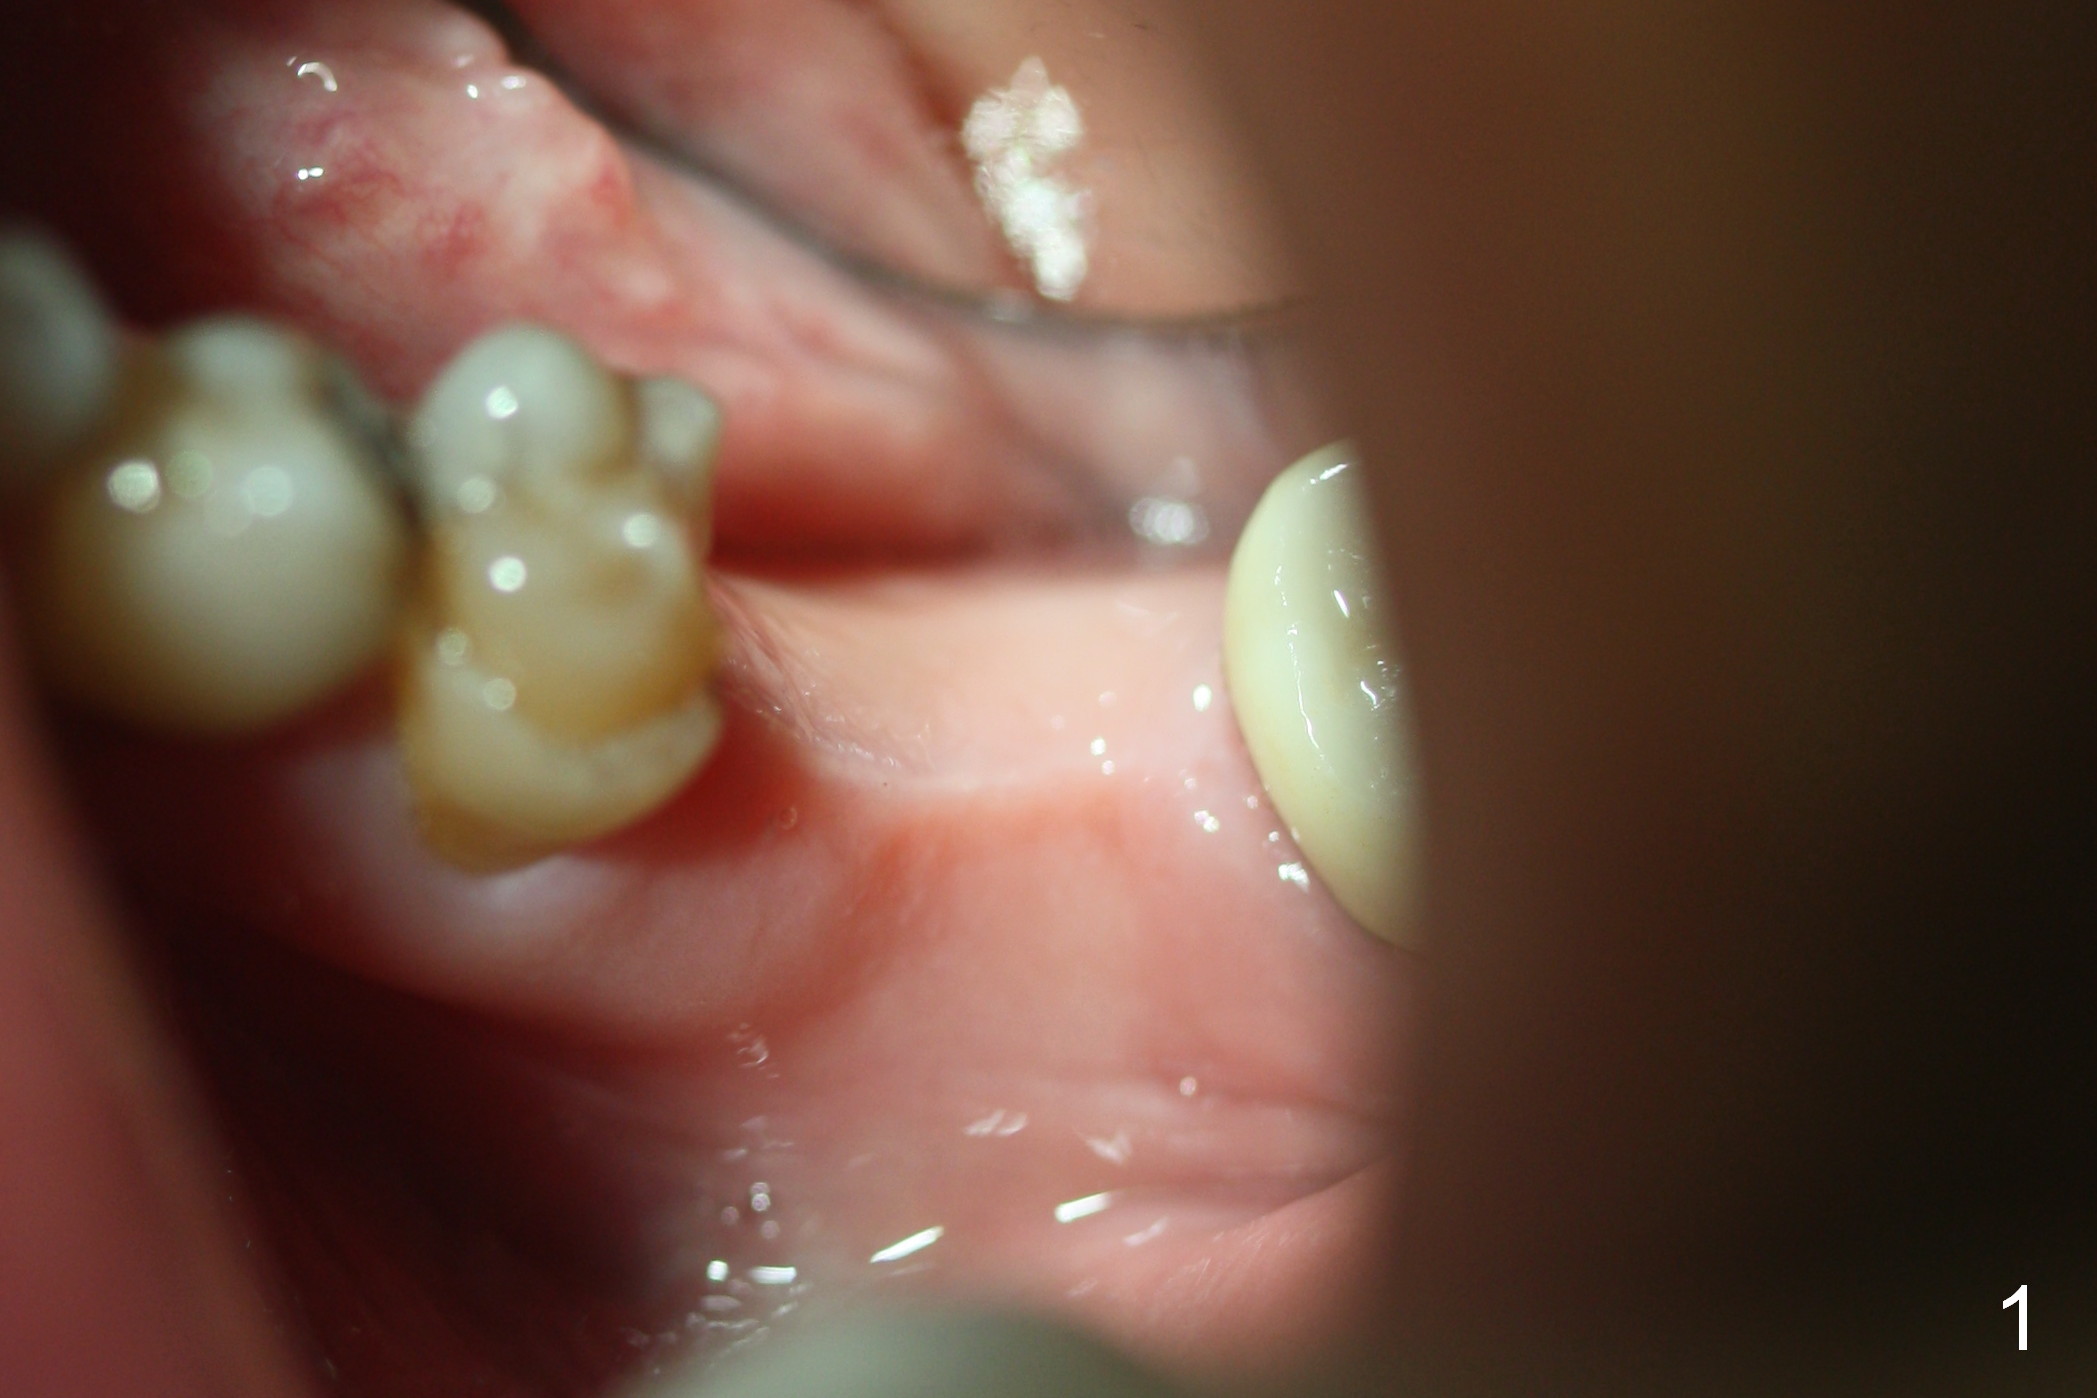

The edentulous ridge at #19 is moderately wide at the base, but pointed at the crest (Fig.1). After raising flaps, it appears that the ridge can hold a 5 mm implant using an implant positioner. The initial osteotomy is 12 mm deep and about 4 mm from the Inferior Alveolar Canal (Fig.2 yellow dashed line). Sequential osteotomy is carried out until 5x12 mm. Because of the pointed crest, 4.5 drill is used to extend the osteotomy at ~ 13 mm so that 12 mm implant can be placed a little deeper to reduce the amount of thread exposure. A 5.3x12 mm implant cannot be seated as deep as expected. A 5.3x10 mm drill with stopper is used before placing the same implant as mentioned above at the desirable depth (Fig.3). The insertion torque is > 60 Ncm. An abutment is placed immediately and an immediate provisional is fabricated and seated. Two to 3 microthreads buccally and lingually are covered by autogenous bone graft and collagen membrane. The patient returns for impression 4 months postop. There is bone loss distally (Fig.4 *). His oral hygiene is excellent. It is hoped that the bone loss will not get worse in the next visit.